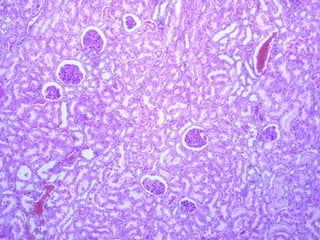

La nefrona o nefrón La nefrona o nefrón es la unidad estructural y funcional fundamental del riñón y en cada riñón humano hay alrededor de 2 millones de ellas. La nefrona consiste en el corpúsculo renal y un sistema de túbulos.

El  corpúsculo renal  constituye el comienzo de la nefrona y está compuesto por un  glomérulo,  que es un ovillo capilar formado por 10 a 20 asas capilares, rodeado por una estructura epitelial bilaminar caliciforme llamada  cápsula renal  o  cápsula de Bowman.  Los capilares glomerulares reciben la sangre desde una  arteriola aferente  y  la envían a una  arteriola eferente  que luego se ramifica para formar una red capilar nueva que irriga los túbulos renales.

Aparato de filtración del riñón El corpúsculo renal es redondeado y tiene un diámetro promedio de 200  μ m. Consiste en un ovillo capilar glomerular y las hojas epiteliales visceral y parietal de la cápsula de Bowman circundante. El aparato de filtración, encerrado por la hoja parietal de la cápsula de Bowman, tiene tres componentes:

Aparato de filtración del riñón Endotelio de los capilares glomerulares,  que posee numerosas fenestraciones. Membrana basal glomerular  (MBG), una lámina basal gruesa (300 a 350 nm) que es el producto conjunto del endotelio y los podocitos, las células de la hoja visceral de la cápsula de Bowman. Hoja visceral de la cápsula de Bowman,  que contiene células especializadas llamadas  células epiteliales viscerales  o  podocitos.

Hoja parietal de la cápsula de Bowman La  hoja parietal de la cápsula de Bowman  contiene  células epiteliales parietales  que forman un epitelio plano simple. En el  polo urinario  del corpúsculo renal se continúa con el epitelio cúbico del  túbulo contorneado proximal . El espacio entre las hojas visceral y parietal de la cápsula de Bowman recibe el nombre de  espacio urinario, espacio capsular  o  espacio de Bowman .

Túbulo contorneado proximal El túbulo   recibe el ultrafiltrado desde el espacio urinario de la cápsula de Bowman. Presenta un  ribete en cepillo  compuesto por micro-vellosidades rectas, largas y muy juntas (luz sucia). Estriaciones básales,  que consisten en mitocondrias alargadas concentradas en las prolongaciones básales y con orientación vertical. La pared del túbulo está formada por una capa de  células cubicas altas  o  cilíndricas bajas  con citoplasma muy eosinófilo y un núcleo central redondo.

Túbulo  contorneado distal El núcleo está ubicado en la región apical y a veces provoca la protrusión de la célula dentro de la luz.  Las células cúbicas grandes del túbulo apenas se tiñen con la eosina y los límites celulares laterales no se ven.  También exhiben una cantidad mucho menor de microvellosidades que están menos desarrolladas que las de las células del túbulo recto proximal.